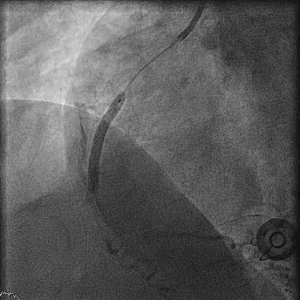

Inhoud: Deze les gaat over de differentiaal diagnose van linker ventrikel hypertrofie (LVH). Wat zijn de oorzaken van LVH? Te denken valt aan de fysiologische adaptaties van de linker ventrikel en de hypertrofische en andere genetische en niet genetische oorzaken. Verder: hoe meet je LVH, wat zijn de gevolgen van LVH en kun je LVH differentiëren met behulp van echocardiografie?